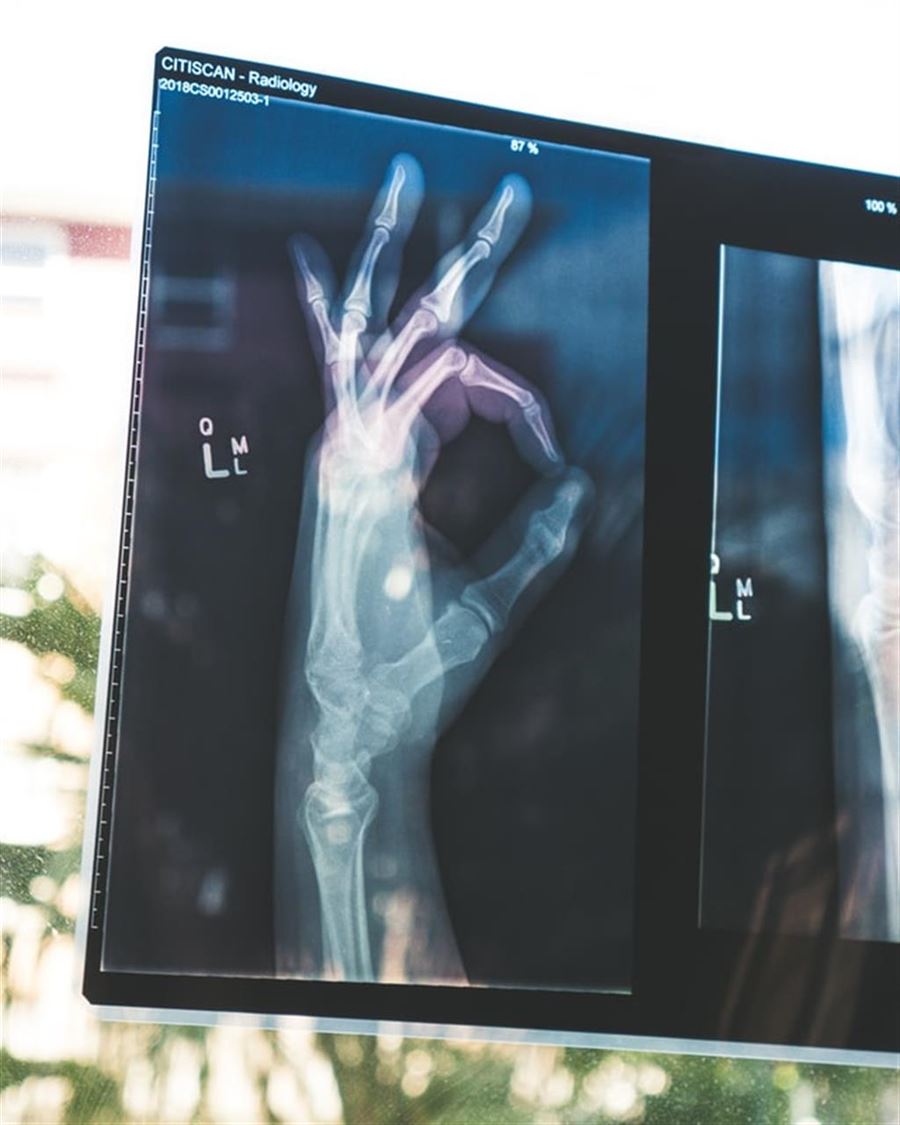

De fleste forbinder nok X-ray med netop sundhedssektoren, hvor det er et vigtigt redskab. X-ray bruges til at bekræfte f.eks. brud på knogler, men bruges også langt mere i dybden. F.eks. kan man i dag anvende store scannere, som kan fortælle, om der er noget der vokser på lungerne eller andet. Det gør det muligt at opdage sygdomme som kræft i bedre tid, så man kan iværksætte et behandlingsforløb.

Som tidligere nævnt er X-ray også brugt hos tandlægen, hvor metoden kan belyse kæben og endda være med til at kortlægge større indgreb – f.eks. i kombination med en 3D-scanner.